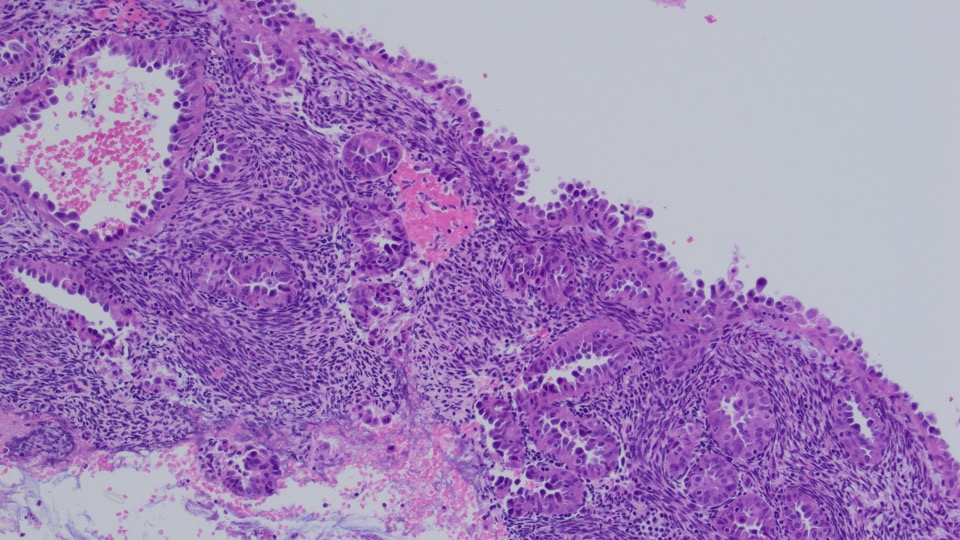

Endometrial curetting specimen show detached aggregates of exuberant architecturally simple papillary/pseudopapillary proliferation of the endometrium.

Papillary proliferation of the endometrium (PPEs) is an uncommon lesion characterized by papillae with fibrovascular stromal cores covered by cytologically benign epithelium. The changes are closely related to hormonal treatment, endometrial polyps, and epithelial metaplasias.